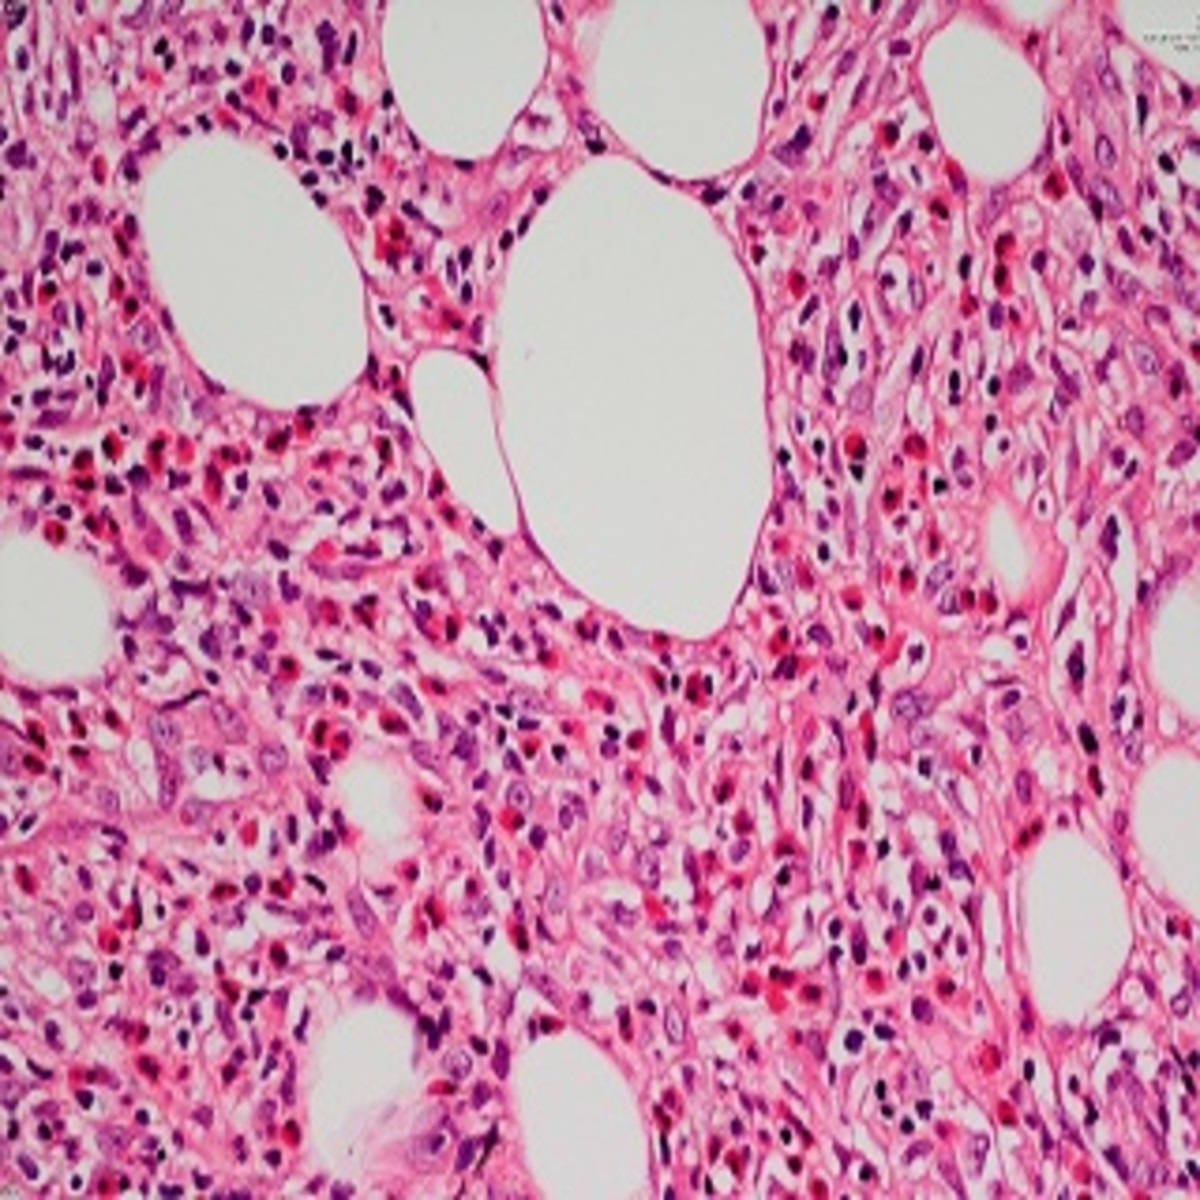

![Eosinophilic Cellulitis PDF] Flame figures associated with eosinophilic dermatosis of hematologic malignancy: is it possible to distinguish the condition from eosinophilic cellulitis in patients with hematoproliferative disease? | Semantic Scholar, image size:1200x672](https://figures.semanticscholar.org/6493287009fa9c164615e725d82a8c7c663c00b5/2-Figure1-1.png)

PDF] Flame figures associated with eosinophilic dermatosis of hematologic malignancy: is it possible to distinguish the condition from eosinophilic cellulitis in patients with hematoproliferative disease? | Semantic Scholar

image size: 1200x672

Frontiers | Eosinophilic dermatosis of hematologic malignancy in patients with chronic lymphocytic leukemia/non-Hodgkin's B lymphoma: a single center prospective clinico-pathological study

image size: 2574x2858